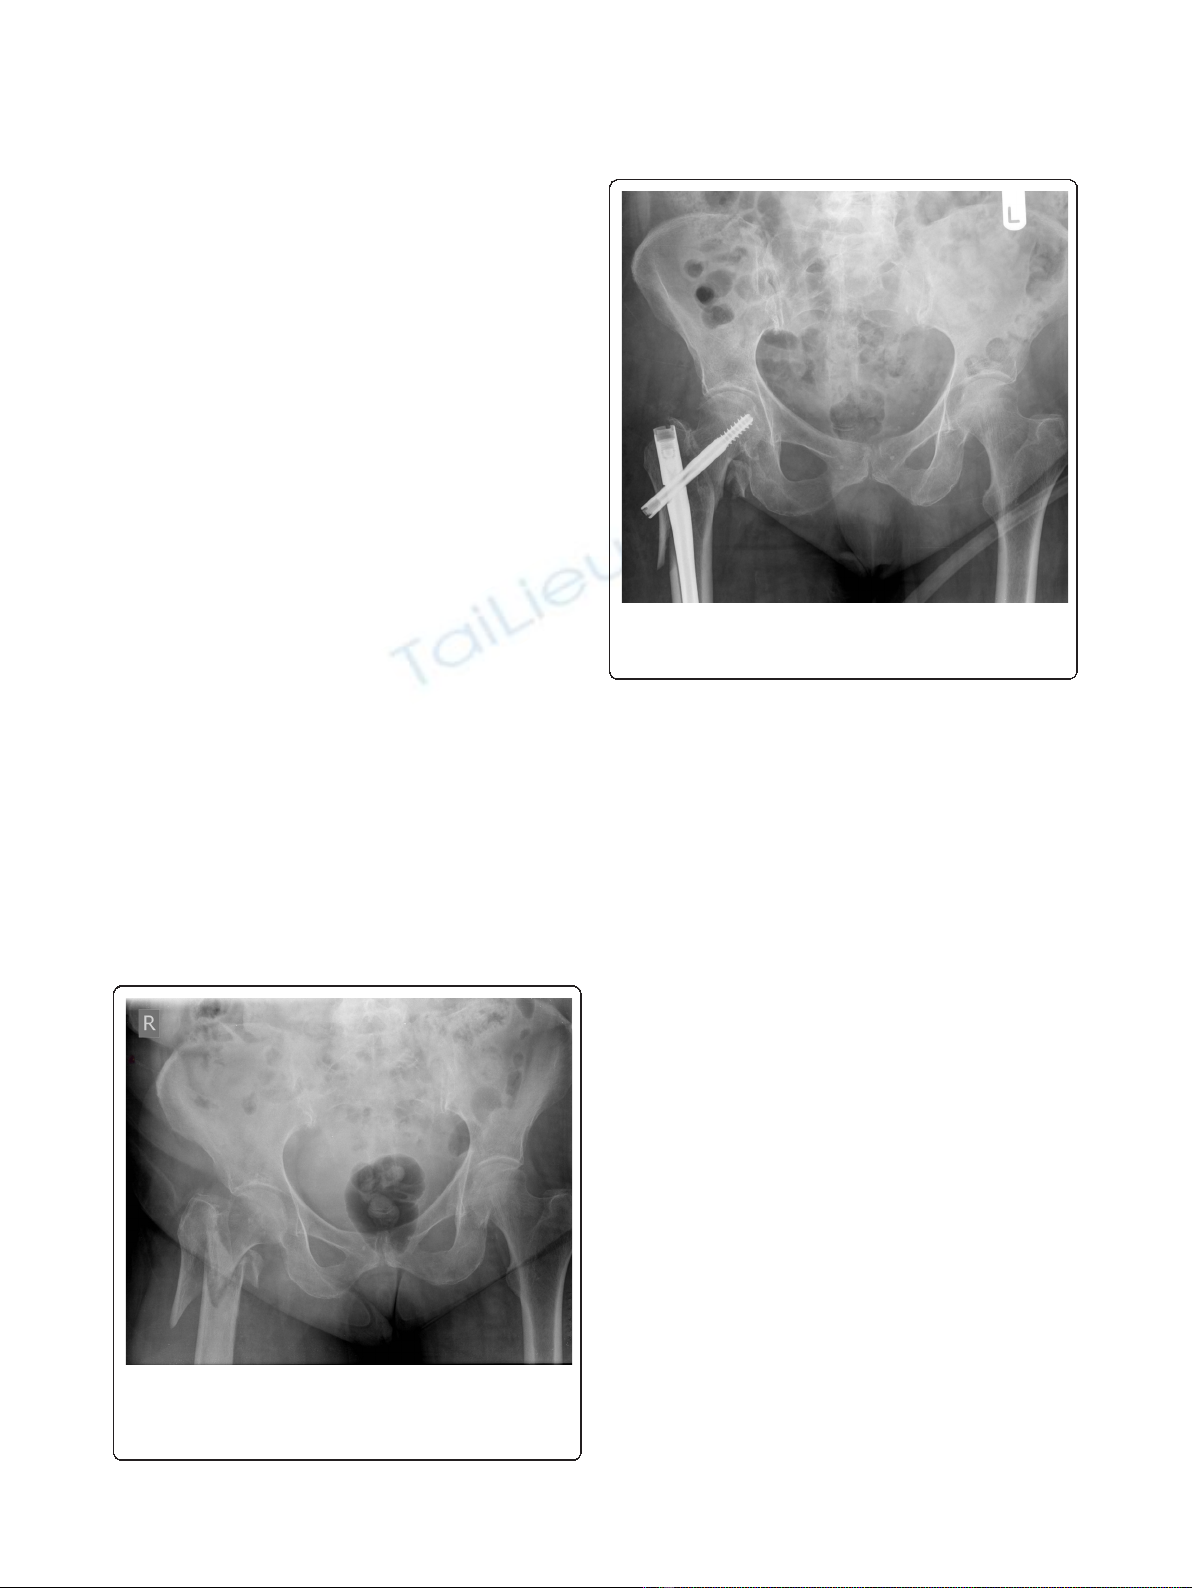

An 80-year-old Caucasian woman sustained a right sub-

system as 31-A3.3 (Figure 1). The fracture was reduced

and stabilized with a TGN (Figure 2). The patient had

Figure 1 Anteroposterior radiograph of the pelvis demonstrating

a right subtrochanteric femoral fracture classified as 31-A3.3

under the AO Foundation (AO)/Orthopaedic Trauma Association

(OTA) fracture classification system.

Figure 2 Anteroposterior radiograph demonstrating reduction

and stabilization of the fracture with a trochanteric gamma

nail (TGN).

Figure 3 Anteroposterior radiograph demonstrating failure of

the TGN with fracture of the proximal end of the nail,

nonunion of the fracture site and varus deformity of the

proximal femur.Figure 4 Lateral radiograph demonstrating failure of the TGN.

Figure 5 Coronal computed tomographic scan confirming the

diagnosis of nonunion at the fracture site.